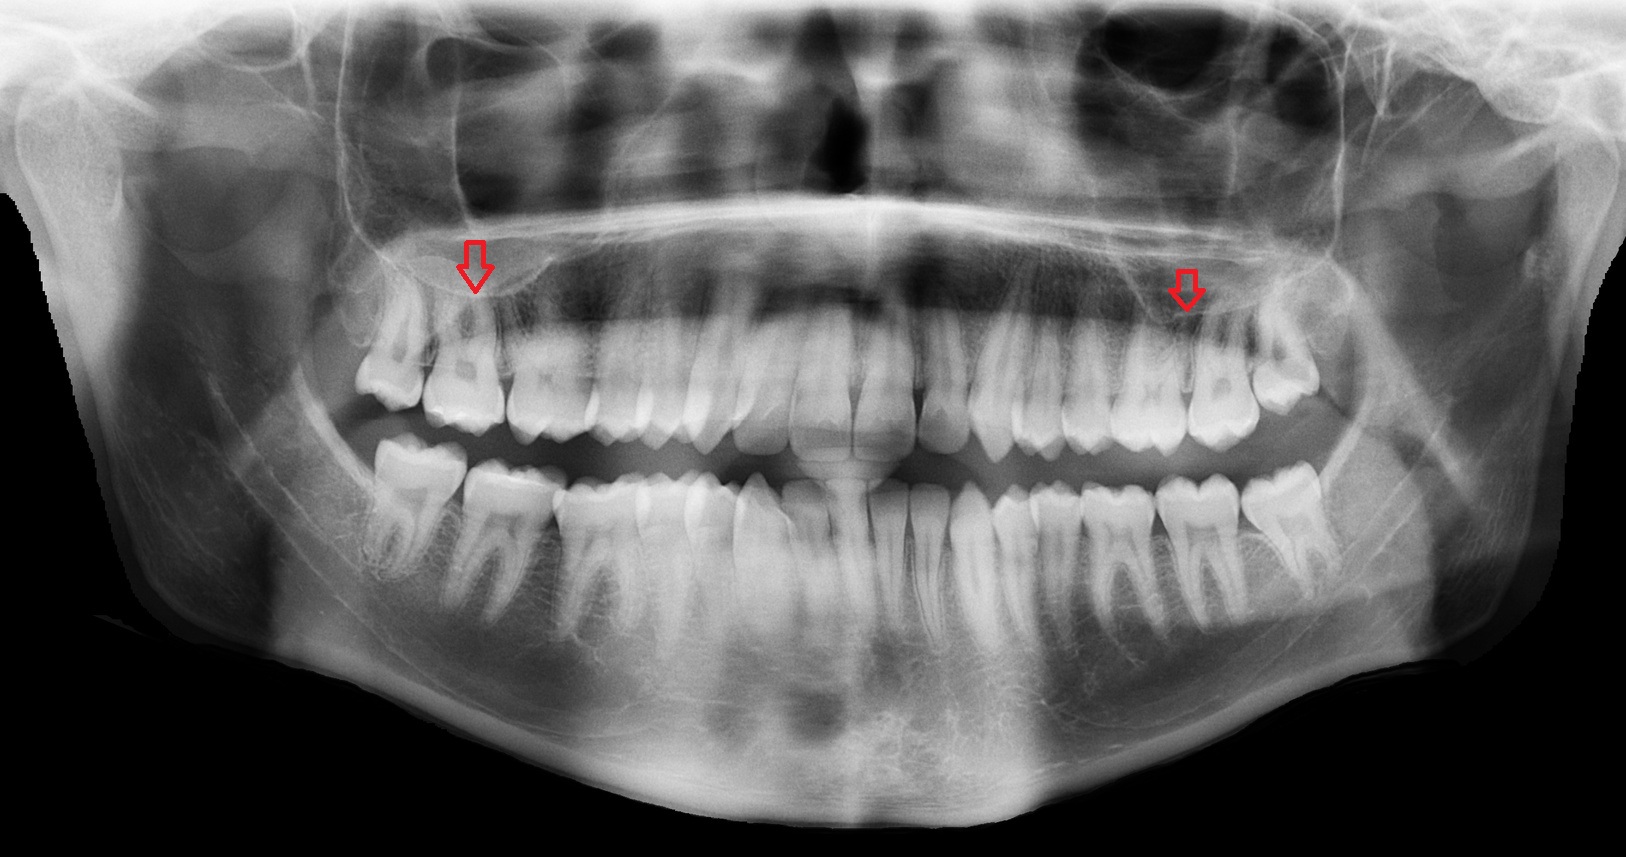

- Root of lower molar tooth

- Root of upper molar tooth